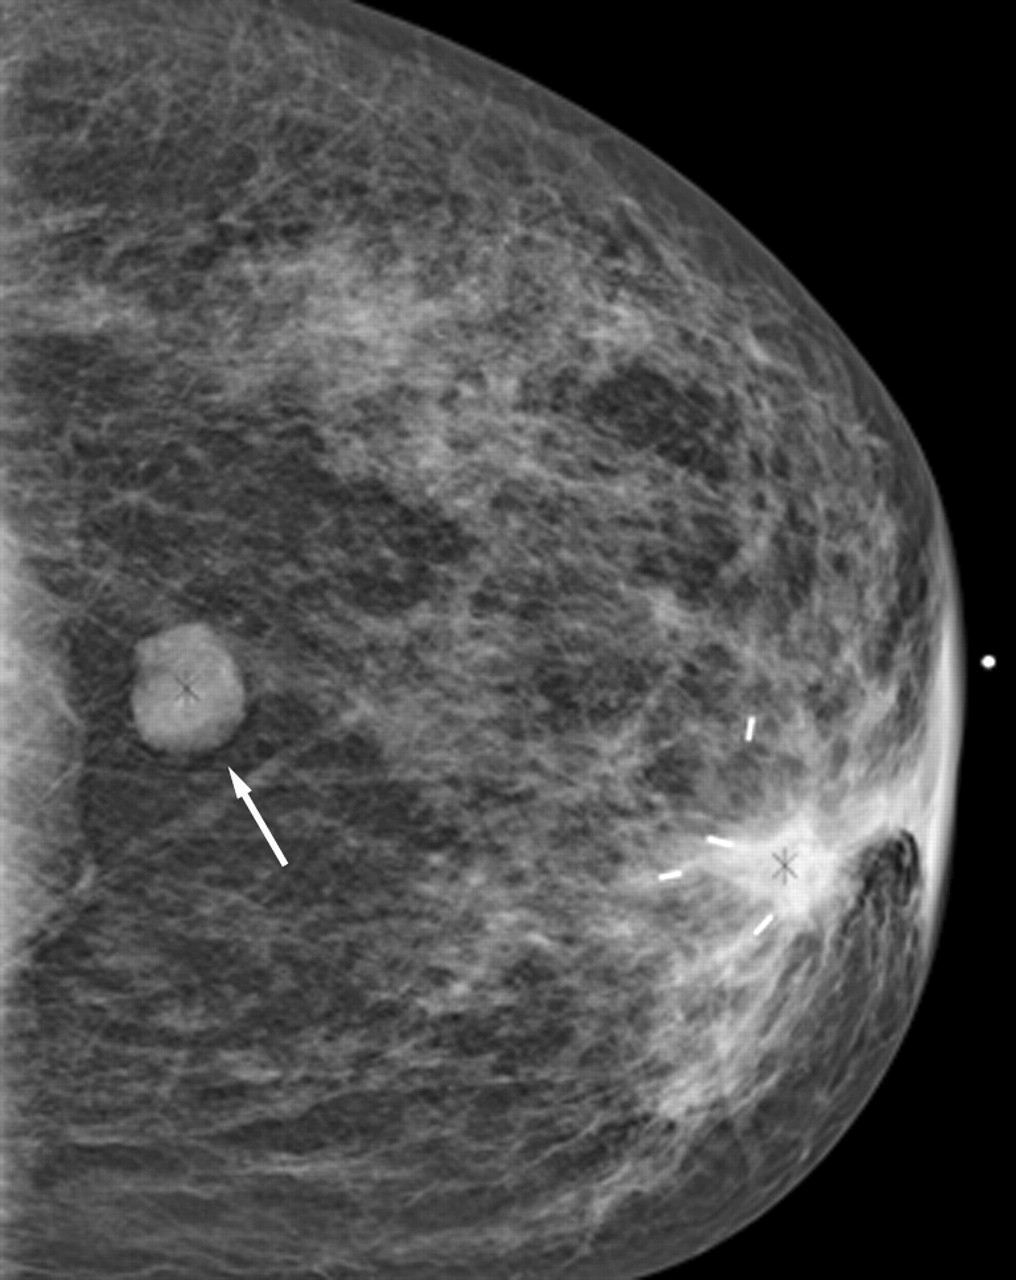

Фиброаденома молочной железы - доброкачественное образование, которое часто встречается у женщин. Оно может быть обнаружено при помощи различных методов диагностики, включая маммографию. Ниже представлены фотографии, помогающие понять, как выглядит данное заболевание.

Маммография и ее роль в диагностике фиброаденомы молочной железы

Маммография - это рентгенологическое исследование молочных желез. Оно позволяет выявить различные изменения в тканях, включая фиброаденому. На маммограммах можно увидеть структурные особенности опухоли и отследить ее динамику во времени.